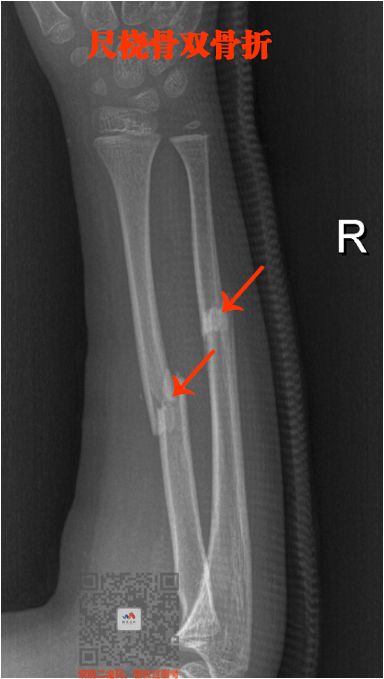

四、长骨骨折

就是四肢的长骨骨折

上肢:

肱骨、尺骨、桡骨

下肢:

股骨、股骨头、胫骨、腓骨

骨折非常简单的

这里就不讲解了,大家看片就行

看片